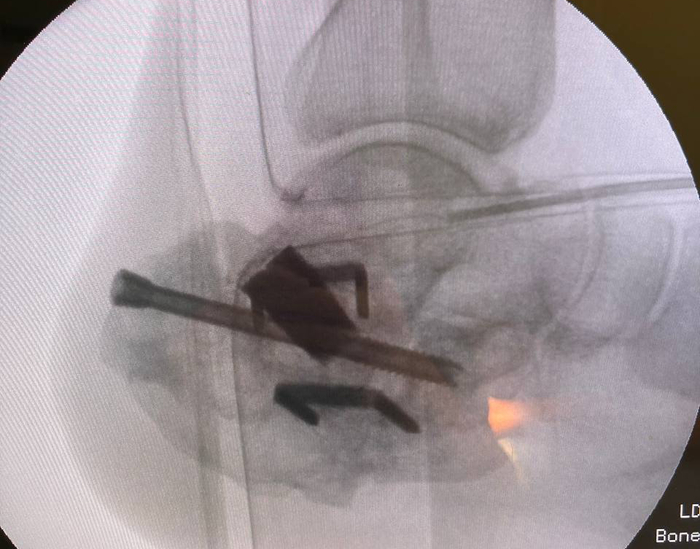

После установки трансплантата и фиксации его press-fit, мы обязательно должны выполнить ЭОП-контроль, чтобы убедиться в корректном положении.

ЭОП-контроль положения трансплантата. Можете обратить внимание, что окончательная дистракция больше чем была на промежуточных снимках.

После костной пластики выполняется фиксация винтами. При этом, я аппарат на данном этапе не демонтирую. Связано это с тем, что из-за компрессии винтов, есть риск избыточного давления сдавления трансплантата, что может привести к последующей резорбции костной ткани в области контакта.

Окончательный вид.

Учитывая, что трансплантаты были установлены press-fit, то посчитал достаточным фиксацию двумя компрессионными винтами, что позволяет добиться абсолютной стабильности в зоне реартродеза.

Результаты рентгенографии, по которым видим, что анатомия пяточной кости восстановлена к максимально нативной. Также устранён субфибурялрный импиджмент синдром. Положение металлоконструкции правильнон.